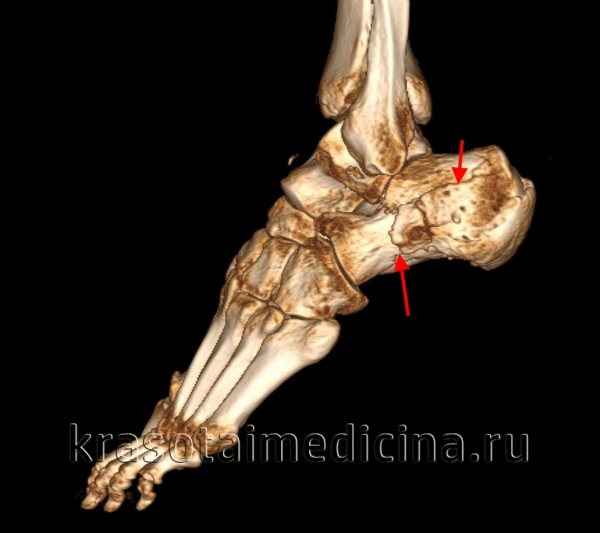

КТ стопы (3D реконструкция). Оскольчатый перелом пяточной кости с разнонаправленным смещением осколков.

- КТ пяточной кости. Позволяет уточнить расположение первичной линии перелома пятки, количество характер и смещения отломков. Назначается для выбора оптимальной тактики лечения. Производится в аксиальной, коронарной и сагиттальной проекциях.